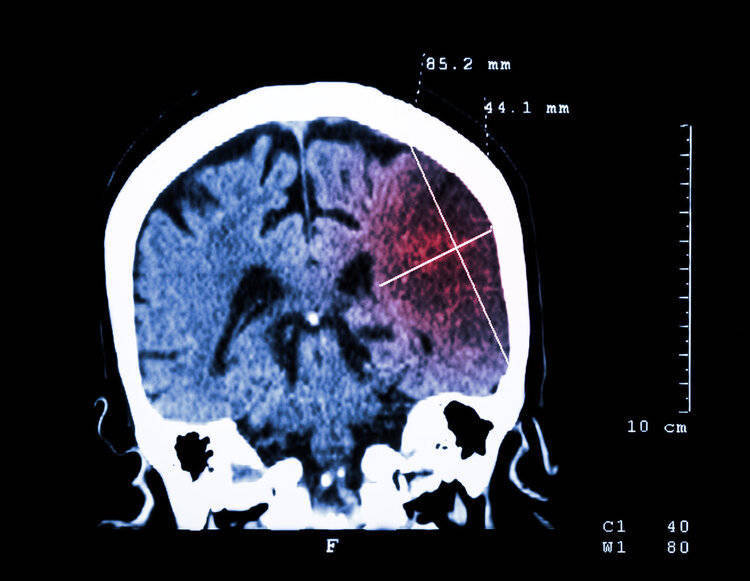

午睡醒来后,王大姨发现我方连水杯王人端不稳,步辇儿时右腿直打晃。见休息也不成缓解,王大姨心生不妙,赶忙让老伴带着她病院。送医后,CT裸露她已突发大面积脑梗。